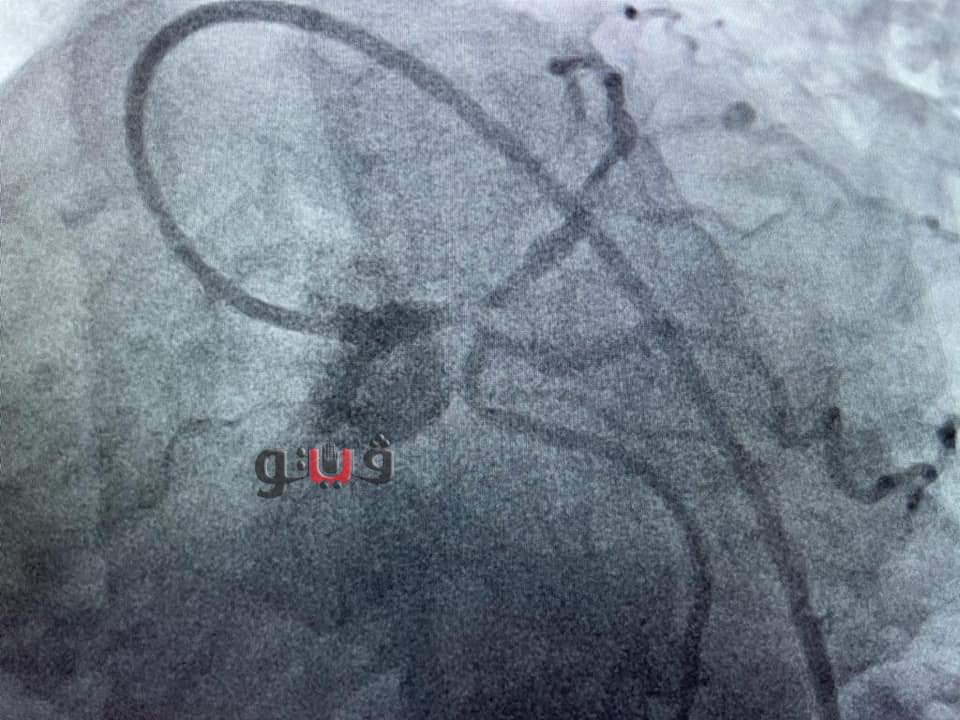

شهد مجمع الإسماعيلية الطبي، التابع لهيئة الرعاية الصحية، اليوم الثلاثاء، إجراء جراحة ناجحة عن طريق إجراء قسطرة قلبية لمسنة تبلغ من العمر ٧٢ عاما باستخدام المنظار الداخلي (I VUS) ، وذلك "دون تحمل المريضة لأي تكاليف" بقيادة الدكتور طارق رشيد، أستاذ القلب والقسطرة القلبية وخبير مرضى الانسداد المزمن للشرايين التاجية.

وكانت المريضة تعاني من ضيق شديد الخطورة بنسبة 95% بالجذع الرئيسي الأيسر للقلب وتم إنقاذها بعد معاناة لمدة أسبوع كامل بحثًا عن مكان تجري فيه جراحة قلب مفتوح أو تركيب دعامات ومبلغ يفوق ال 100 ألف جنيه للعلاج بأحد المستشفيات الخاصة، وكادت أن تفارق الحياة نظرًا لخطورة حالتها الصحية الشديدة.

وصلت المريضة إلى مجمع الإسماعيلية الطبي حيث تم علاجها على يد فريق من أمهر أطباء القلب والقساطر القلبية بمستشفيات هيئة الرعاية الصحية، دون تحملها أي أعباء مالية، وتم إجراء العملية بنجاح.